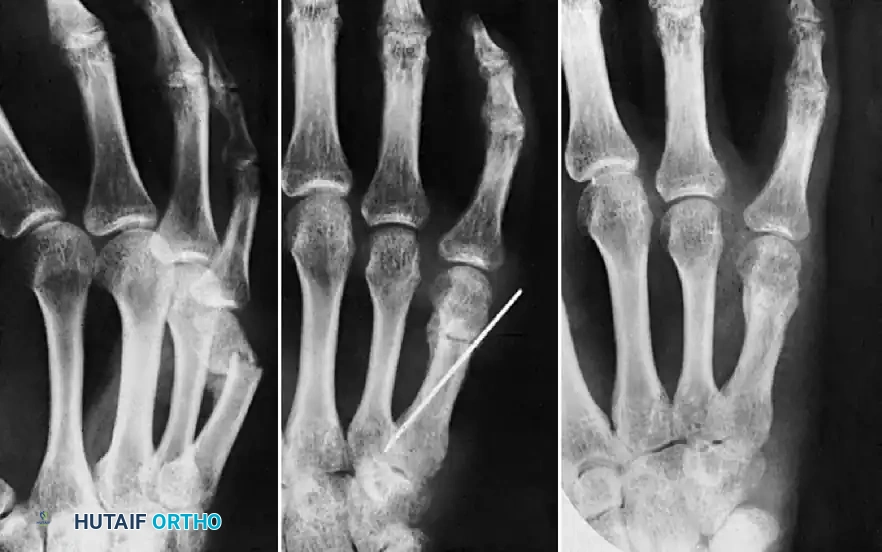

FIGURE 67-73: A, Malunited phalangeal fracture. B, Result is satisfactory after treatment by osteotomy and fixation with a medullary bone peg.

FIGURE 67-75: A, Malunited phalangeal fracture with rotational deformity. B, After treatment by osteotomy through the proximal end of the bone and fixation with two Kirschner wires. Healing is usually more rapid after osteotomy at this metaphyseal level than after one at the old diaphyseal fracture site.

FIGURE 67-70: A, Malunited fracture of the base of the middle phalanx with splaying of the volar and dorsal articular surfaces. B, After wedge resection of the bone, the volar and dorsal fragments were held securely with cerclage wire fixation.